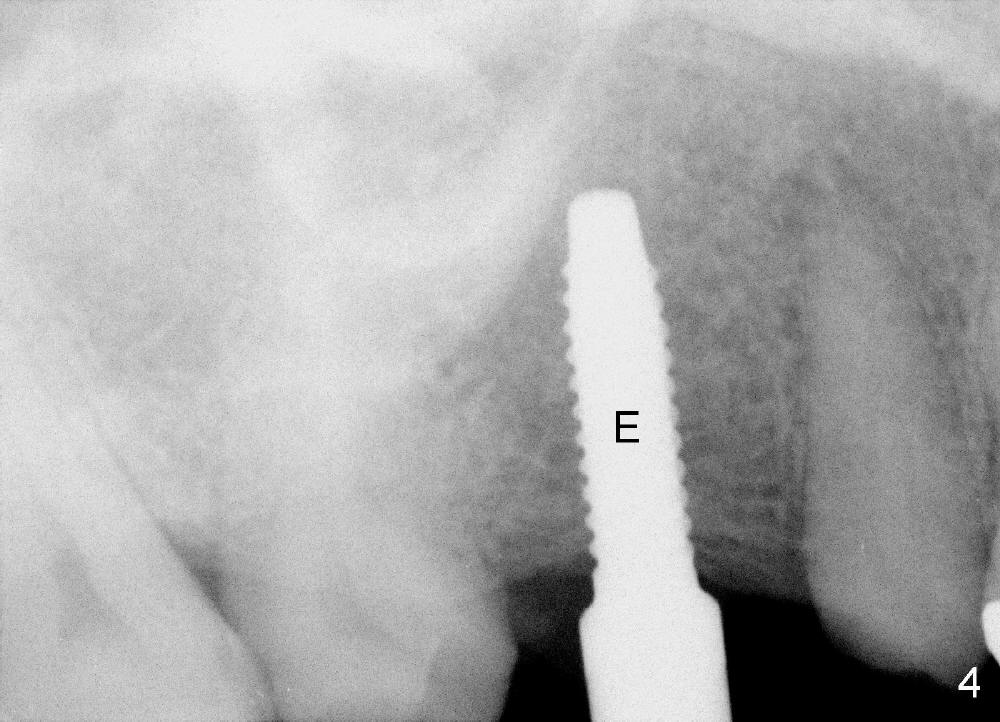

The bone density (Fig.1 white *) at the edentulous area (#3) is lower than that at the dentulous one (black *, 50 year-old man). The buccal plate is also atrophic and concave (Fig.2,3 arrowheads). A series of bone expanders are used to form osteotomy (following 1.6 mm pilot drill) at the depth of 14 mm (Fig.3 E 3.0 mm in diameter). When the last expander (4.3 mm) is removed from the osteotomy, the buccal plate appears to have been moved buccally (Fig.5 arrowheads). A 5.3x14 mm submerged implant (Fig.6 I) is placed with insertion torque >35 Ncm. The buccal plate seems to improve following placement of an 8.2 mm healing abutment and suturing (Fig.7). No bone graft is used. The buccal plate remains normal 12 days postop (Fig.8). It is slightly concave 3 months postop (Fig.9) with minimal bone resorption at the crest (Fig.10 (H: healing abutment),11 (A: cemented abutment). Nine months post cementation (12 months postop), bone resorption at the crest remains minimal (Fig.12) while the buccal plate (Fig.13 *) at #3 remains strong. Bone loss appears not to get worse 22 months post cementation (Fig.14). Soft and hard tissues remain healthy around the implant crown 3 years (Fig.15) and 3.5 years (Fig.16,17) post cementation.